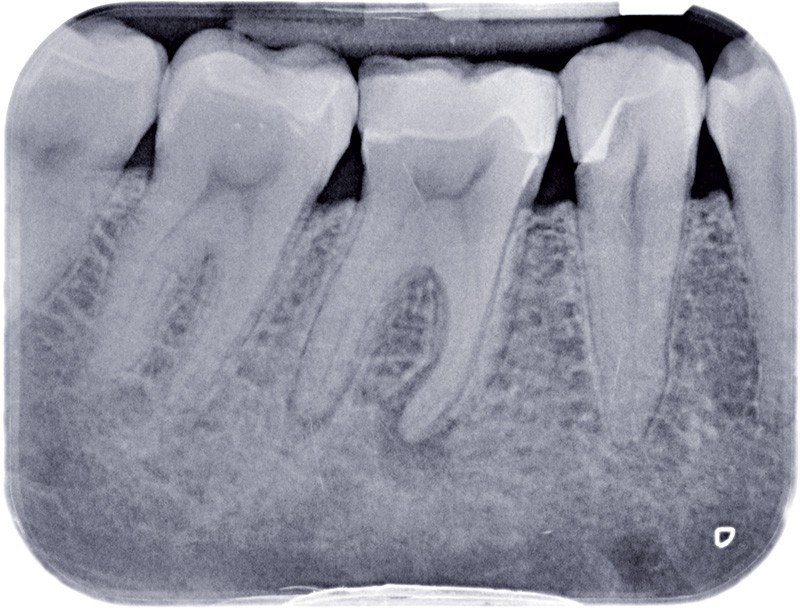

L’OBTURATION CANALAIRE

L’obturation tridimensionnelle canalaire permet de maintenir l’état de désinfection obtenu lors de la préparation chimiomécanique. C’est l’obturation complète de l’ensemble du réseau canalaire, aussi près que possible de la jonction cémentodentinaire. Elle fait partie intégrante de la triade endodontique dont les deux autres composantes sont la mise en forme et l’irrigation. Le praticien est amené à se poser la question suivante : quelle technique d’obturation choisir ? La vraie problématique réside dans la mise en forme. En effet, un canal mal mis en forme sera mal nettoyé et par conséquent mal obturé. Ainsi, les différents…